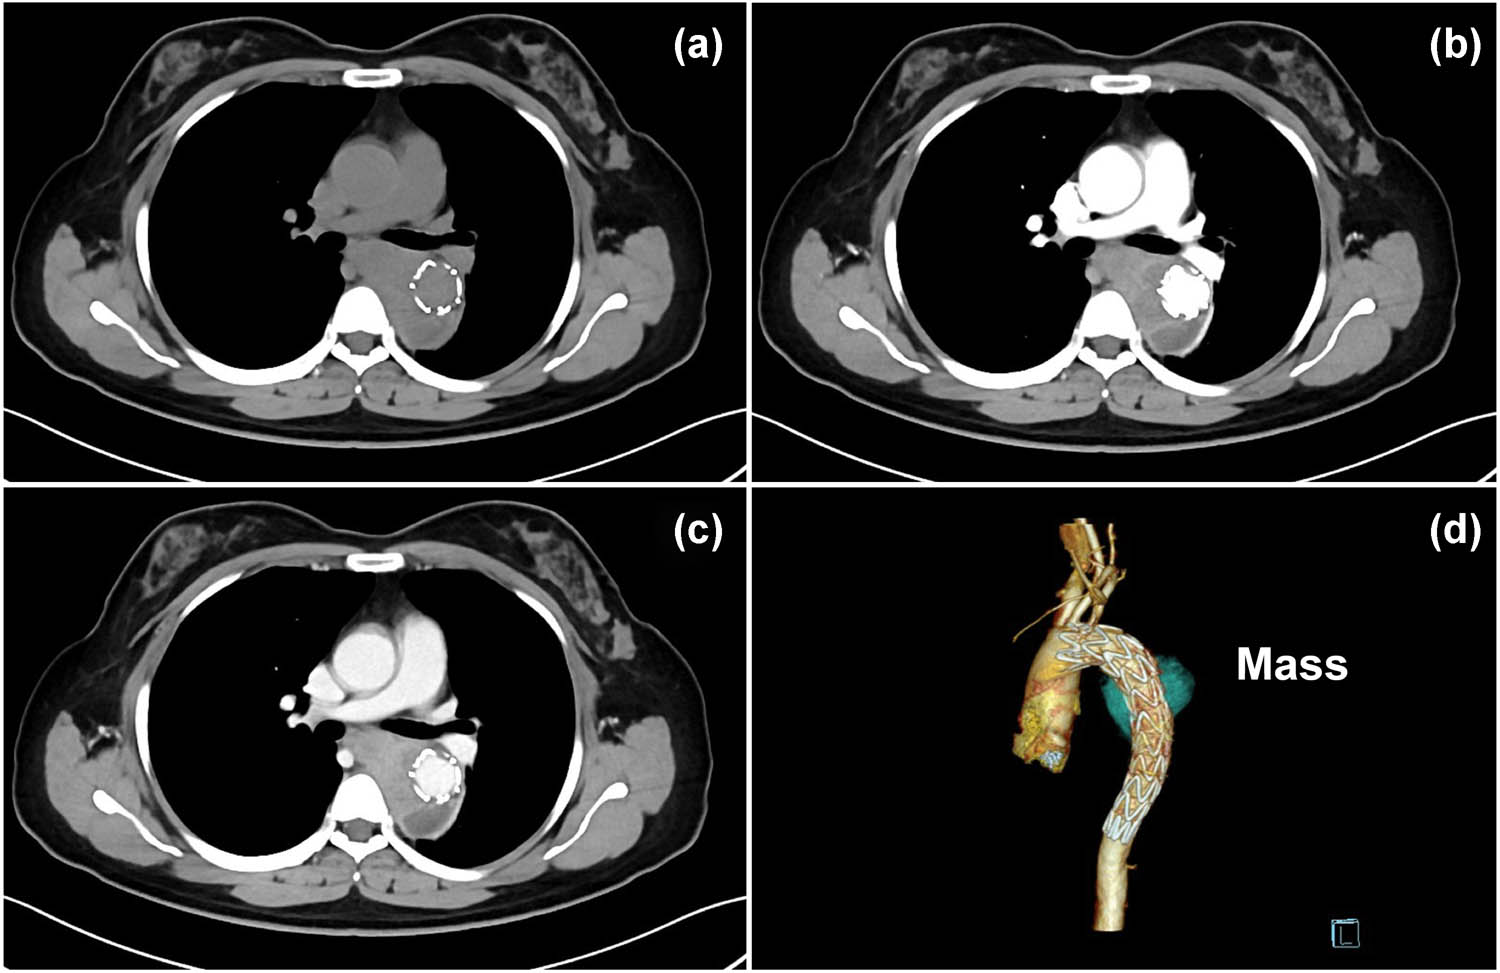

Three months after endovascular stent graft implantation, follow-up CTA (Figure 3) showed enlargement of the false lumen with nonhomogeneous enhancement and mediastinal extensions. The patient was interpreted by radiologists as having an endoleak and periaortic/mediastinal hematoma, which were also considered by other medical centers during follow-up. However, seven months later, the patient was readmitted to the hospital with complaints of dysphagia and dyspnea. Subsequent magnetic resonance imaging (Figure 4) showed gradual enlargement of the false lumen with mediastinal extensions and new lesions in the azygos vein. Angiogenic hemangioma was suspected, and endobronchial ultrasound biopsy was performed to confirm the lesion. Histopathological evaluation indicated an intimal sarcoma (Figure 5). Immunohistochemical staining for vimentin, CD10, CD68, and CD99 was positive, whereas that for S-100, CD56, desmin, CD30, CD15, leukocyte common antigen, smooth muscle actin, CD34, CD61, and CD5 was negative. Afterwards, she received adjuvant chemotherapy with a combined treatment of ifosfamide and epirubicin; however, the general condition of the patient rapidly deteriorated after 1 cycle of adjuvant chemoradiotherapy, and she died exactly 19 months after the initial hospitalization.

Axial nonenhanced CT image (a) and CTA (b–d) showing enlargement of the false lumen three months after stent implantation, with nonhomogeneous enhancement and mediastinal extensions of the false lumen, which was interpreted by radiologists in our hospital and other medical centers during follow-up as an endoleak and periaortic hematoma.